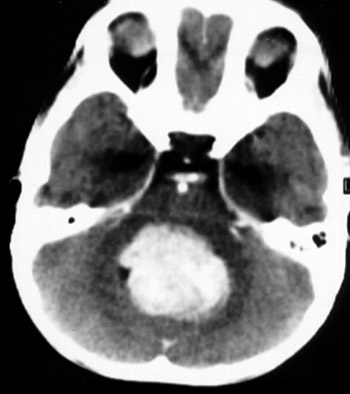

This enhanced CT scan demonstrates a medulloblastoma arising in the cerebellar vermis in a child. These may extend into the fourth ventricle and may seed the neuraxis.